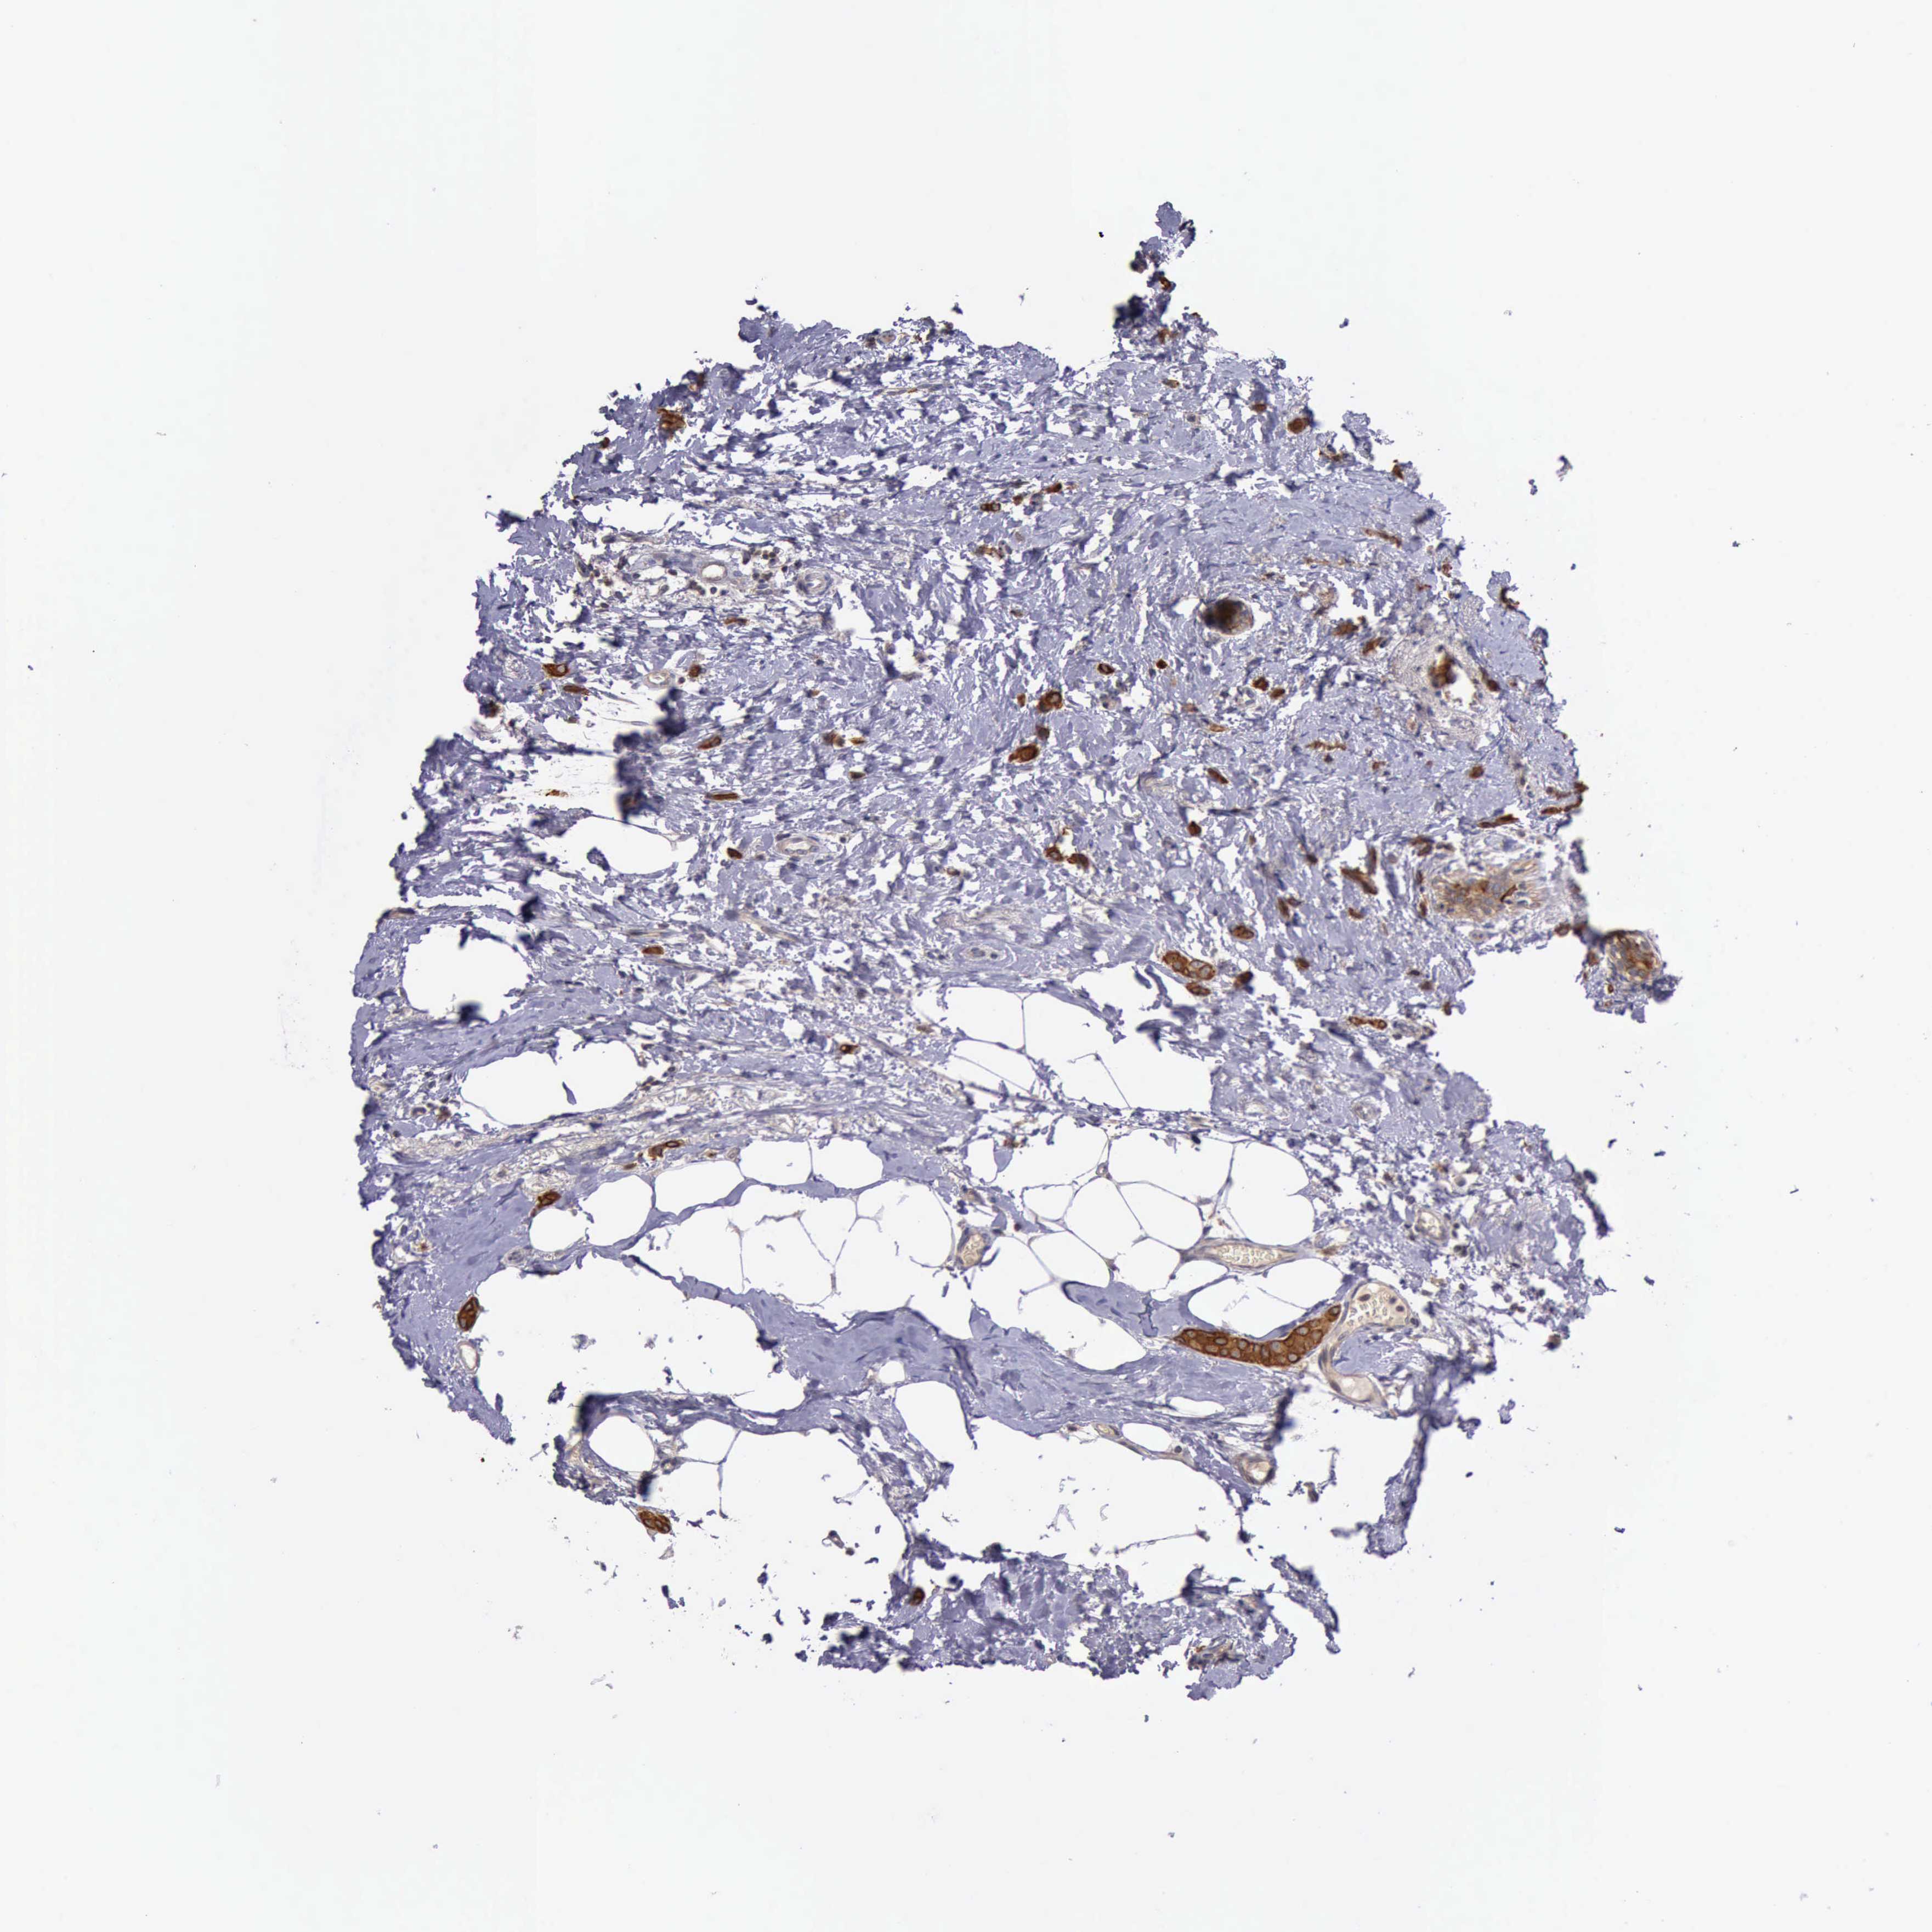

CANCER BREAST CANCER Show tissue menu

BRCA TCGA BRCA VALIDATION PROTEIN EXPRESSION

ANTIBODIES

AND

VALIDATION